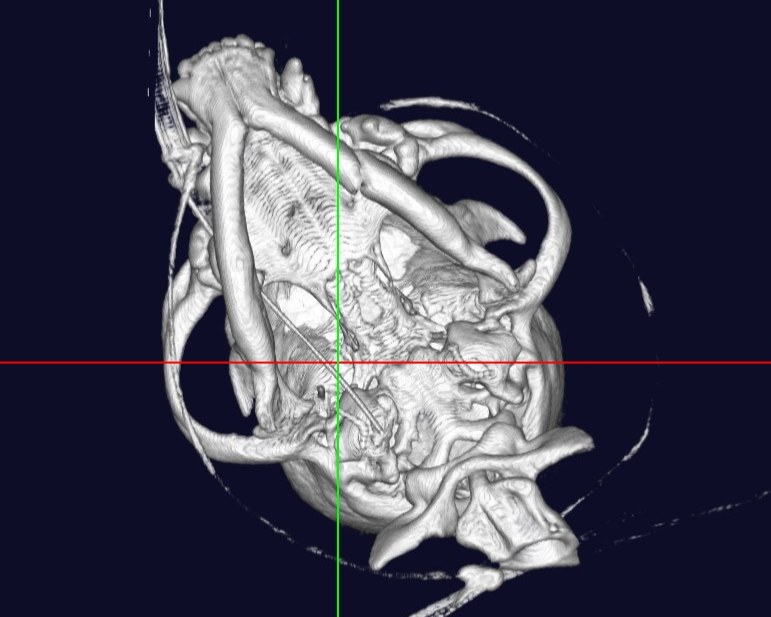

犬 椎間板ヘルニア

フェレット 血管造影